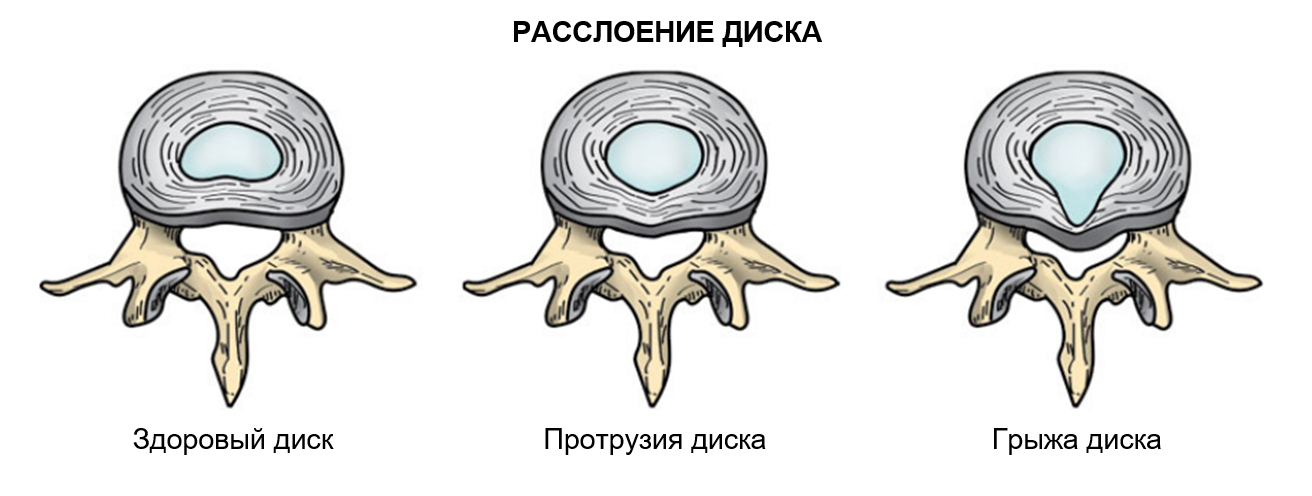

КТ-протрузии дисков: Визуализация и классификация